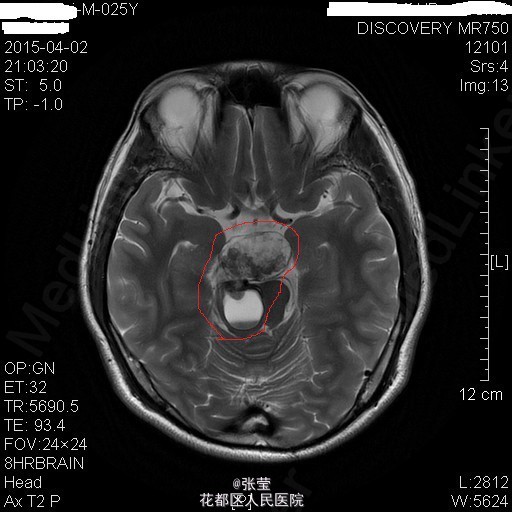

青年男性,主诉:头晕伴肢体乏力1周。 现病史:患者1周前始无明显诱因反复出现头晕,伴左侧肢体乏力、行走不稳,偶伴头痛、恶心感,休息后可稍缓解,无呕吐,无天旋地转感,无晕厥,无伴听力、记忆力减退等,发作无明显规律。至当地医院就诊,头部MR结果示:右间脑下方-脑干-桥前池-左鞍底区肿瘤,并瘤内卒中。

查体:神清,对答切题,双瞳等大等圆,直径约3mm,对光反射灵敏,双侧听力粗测正常,四肢肌力Ⅴ级。生理反射存在,病理征未引出。 辅查:颅脑MR:1、斜坡区占位,侵及中脑、脑桥右份及蝶窦,病灶ADC值增高,FA值下降,考虑脊索瘤并囊变、出血可能大。 2、MRA示双侧颈内动脉向外侧移位,余脑动脉未见明确异常。